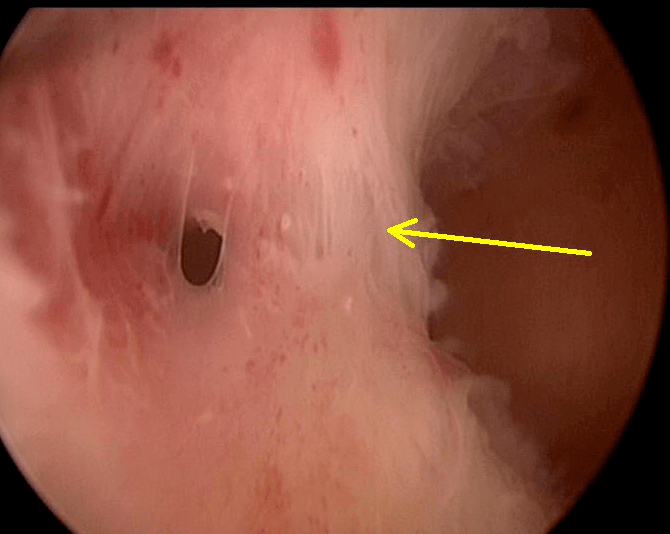

不良孕史+引產!後續備孕細說我做宮腔鏡手術的詳細歷程

本人2016年有過不良孕史,17周的時候引產。之後半年都沒來月經,芬嗎通吃過,孕酮也打過,中藥也吃過也不來。去年三月去做了宮腔鏡檢查,宮腔粘連,但因為是門診檢查的,醫生只做了簡單處理把一些纖維性的粘黏給剪開了。但告知我仍有肌性粘黏,因不是完全粘黏,可以先試著懷孕,必要時再做手術。長達一年的備孕經歷我是做了門診宮腔鏡後的次月來的月經,經量少的可憐,一天連一張護墊都裝不滿,而且顏色發黑。期間各種吃中藥...